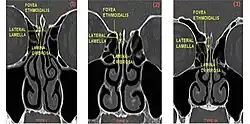

From left to right, Keros type I, II, and III.

The Keros classification is a method of classifying the depth of the olfactory fossa.

The depth of the olfactory fossa is determined by the height of the lateral lamella of the cribriform plate. Keros in 1962, classified the depth into three categories.[3]

• type 1: has a depth of 1–3 mm (26.3% of population)

• type 2: has a depth of 4–7 mm (73.3% of population)

• type 3: has a depth of 8–16 mm (0.5% of population)

• type 4: has asymmetric depths (described by Stammberger)